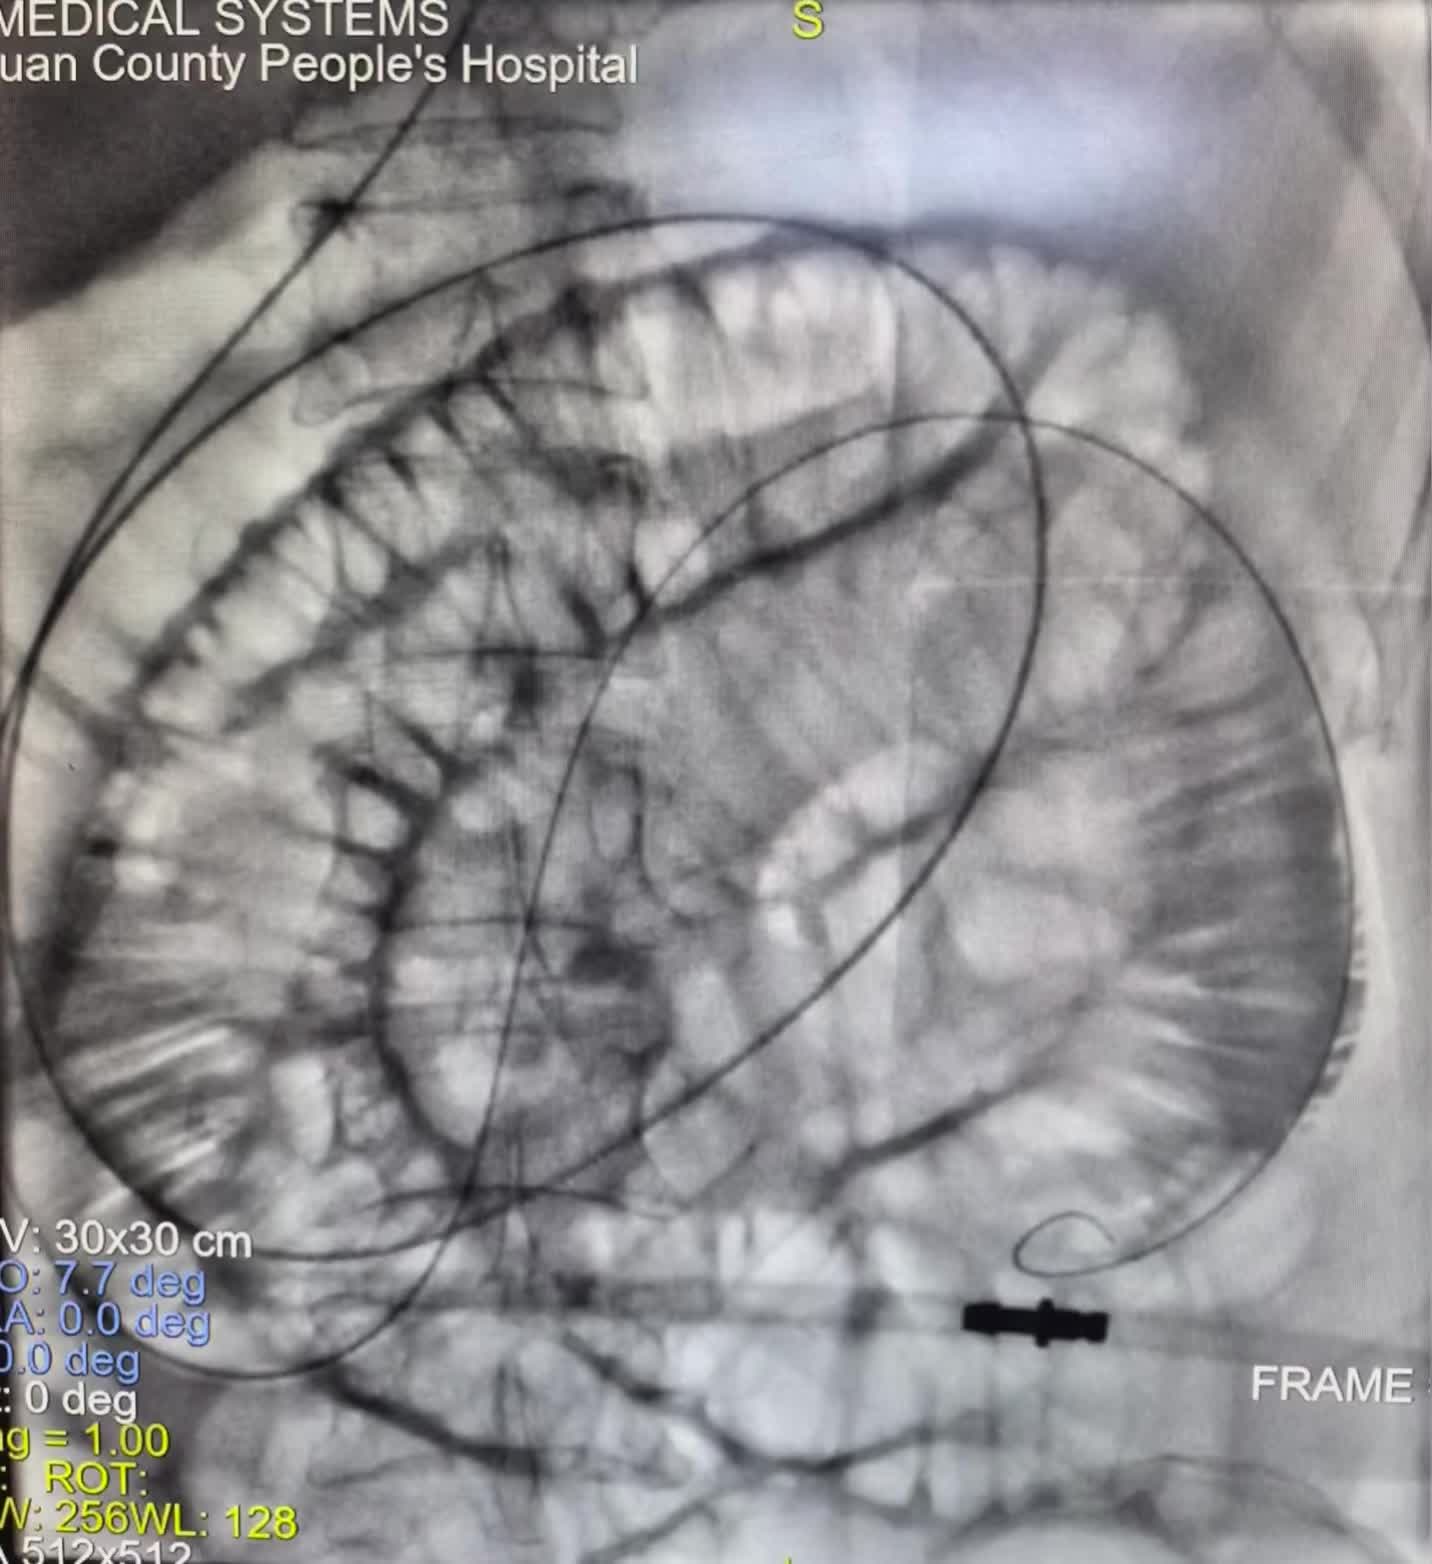

直肠癌术后3年,近期反复肠梗阻,胃管减压 直肠癌术后3年,近期反复肠梗阻,胃管减压1周,效果欠佳。今日在DSA可视化行肠管黏连松紧,及肠道减压管置入,直肠吻合狭窄扩张术,术后即可通便通气,腹胀,腹痛即可减轻。口。DSA可视化经鼻经肛双向开通,松解黏连介入治疗技术,安全有效,经自然腔道无创操做效果立竿见影。